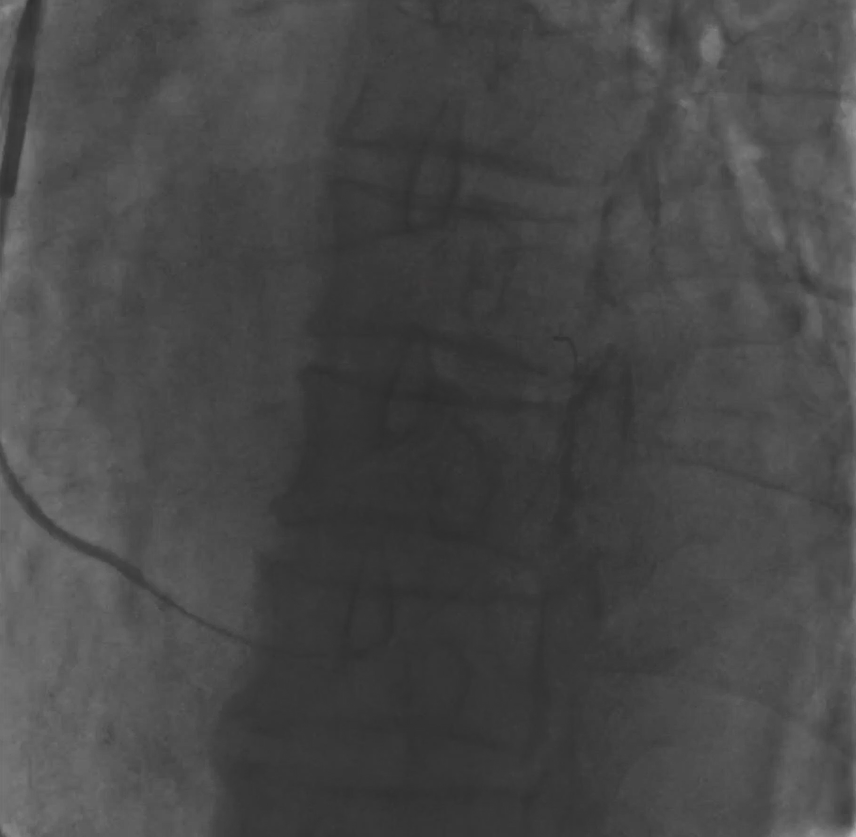

确定开口位置之后,发现CS开口朝下,首先尝试利用AL1+泥鳅导丝寻找冠状窦,反复几次均无法进入,更换AL2+泥鳅成功进入冠状窦。

图四 AL2+泥鳅进入冠状窦